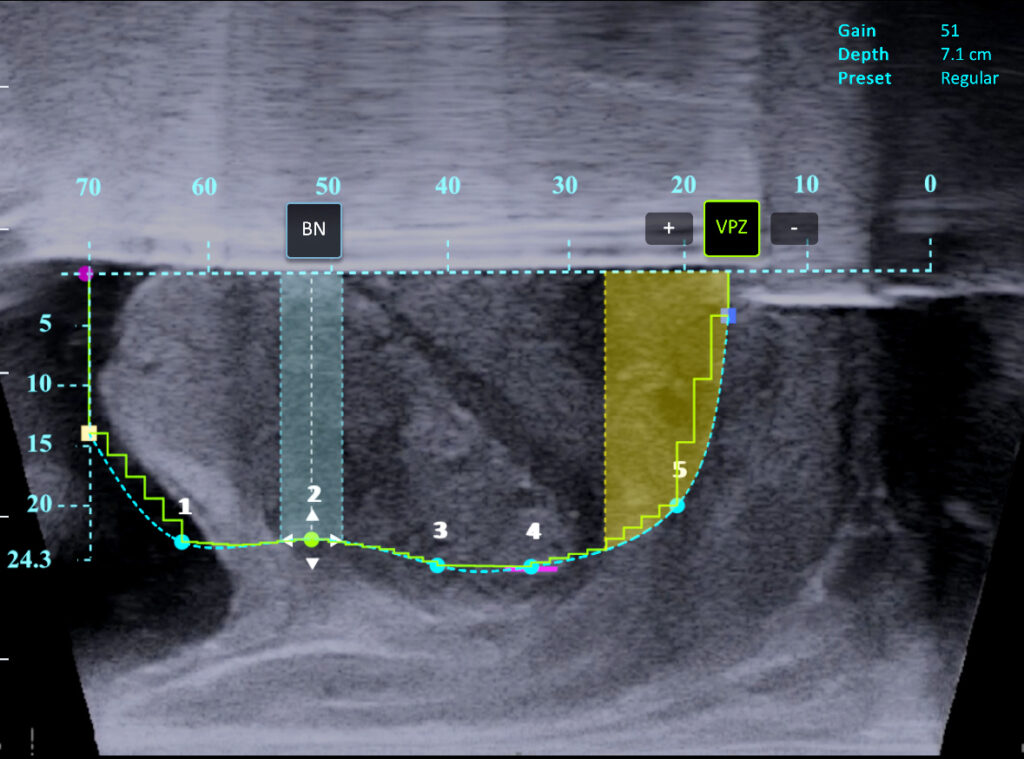

Real-time image guidance

Intraoperative ultrasound imaging combined with cystoscopy enables identification of critical anatomy.

Personalized treatment planning

Computer-assisted planning allows the surgeon to maximize tissue resection while sparing the bladder neck, verumontanum, and external sphincter.